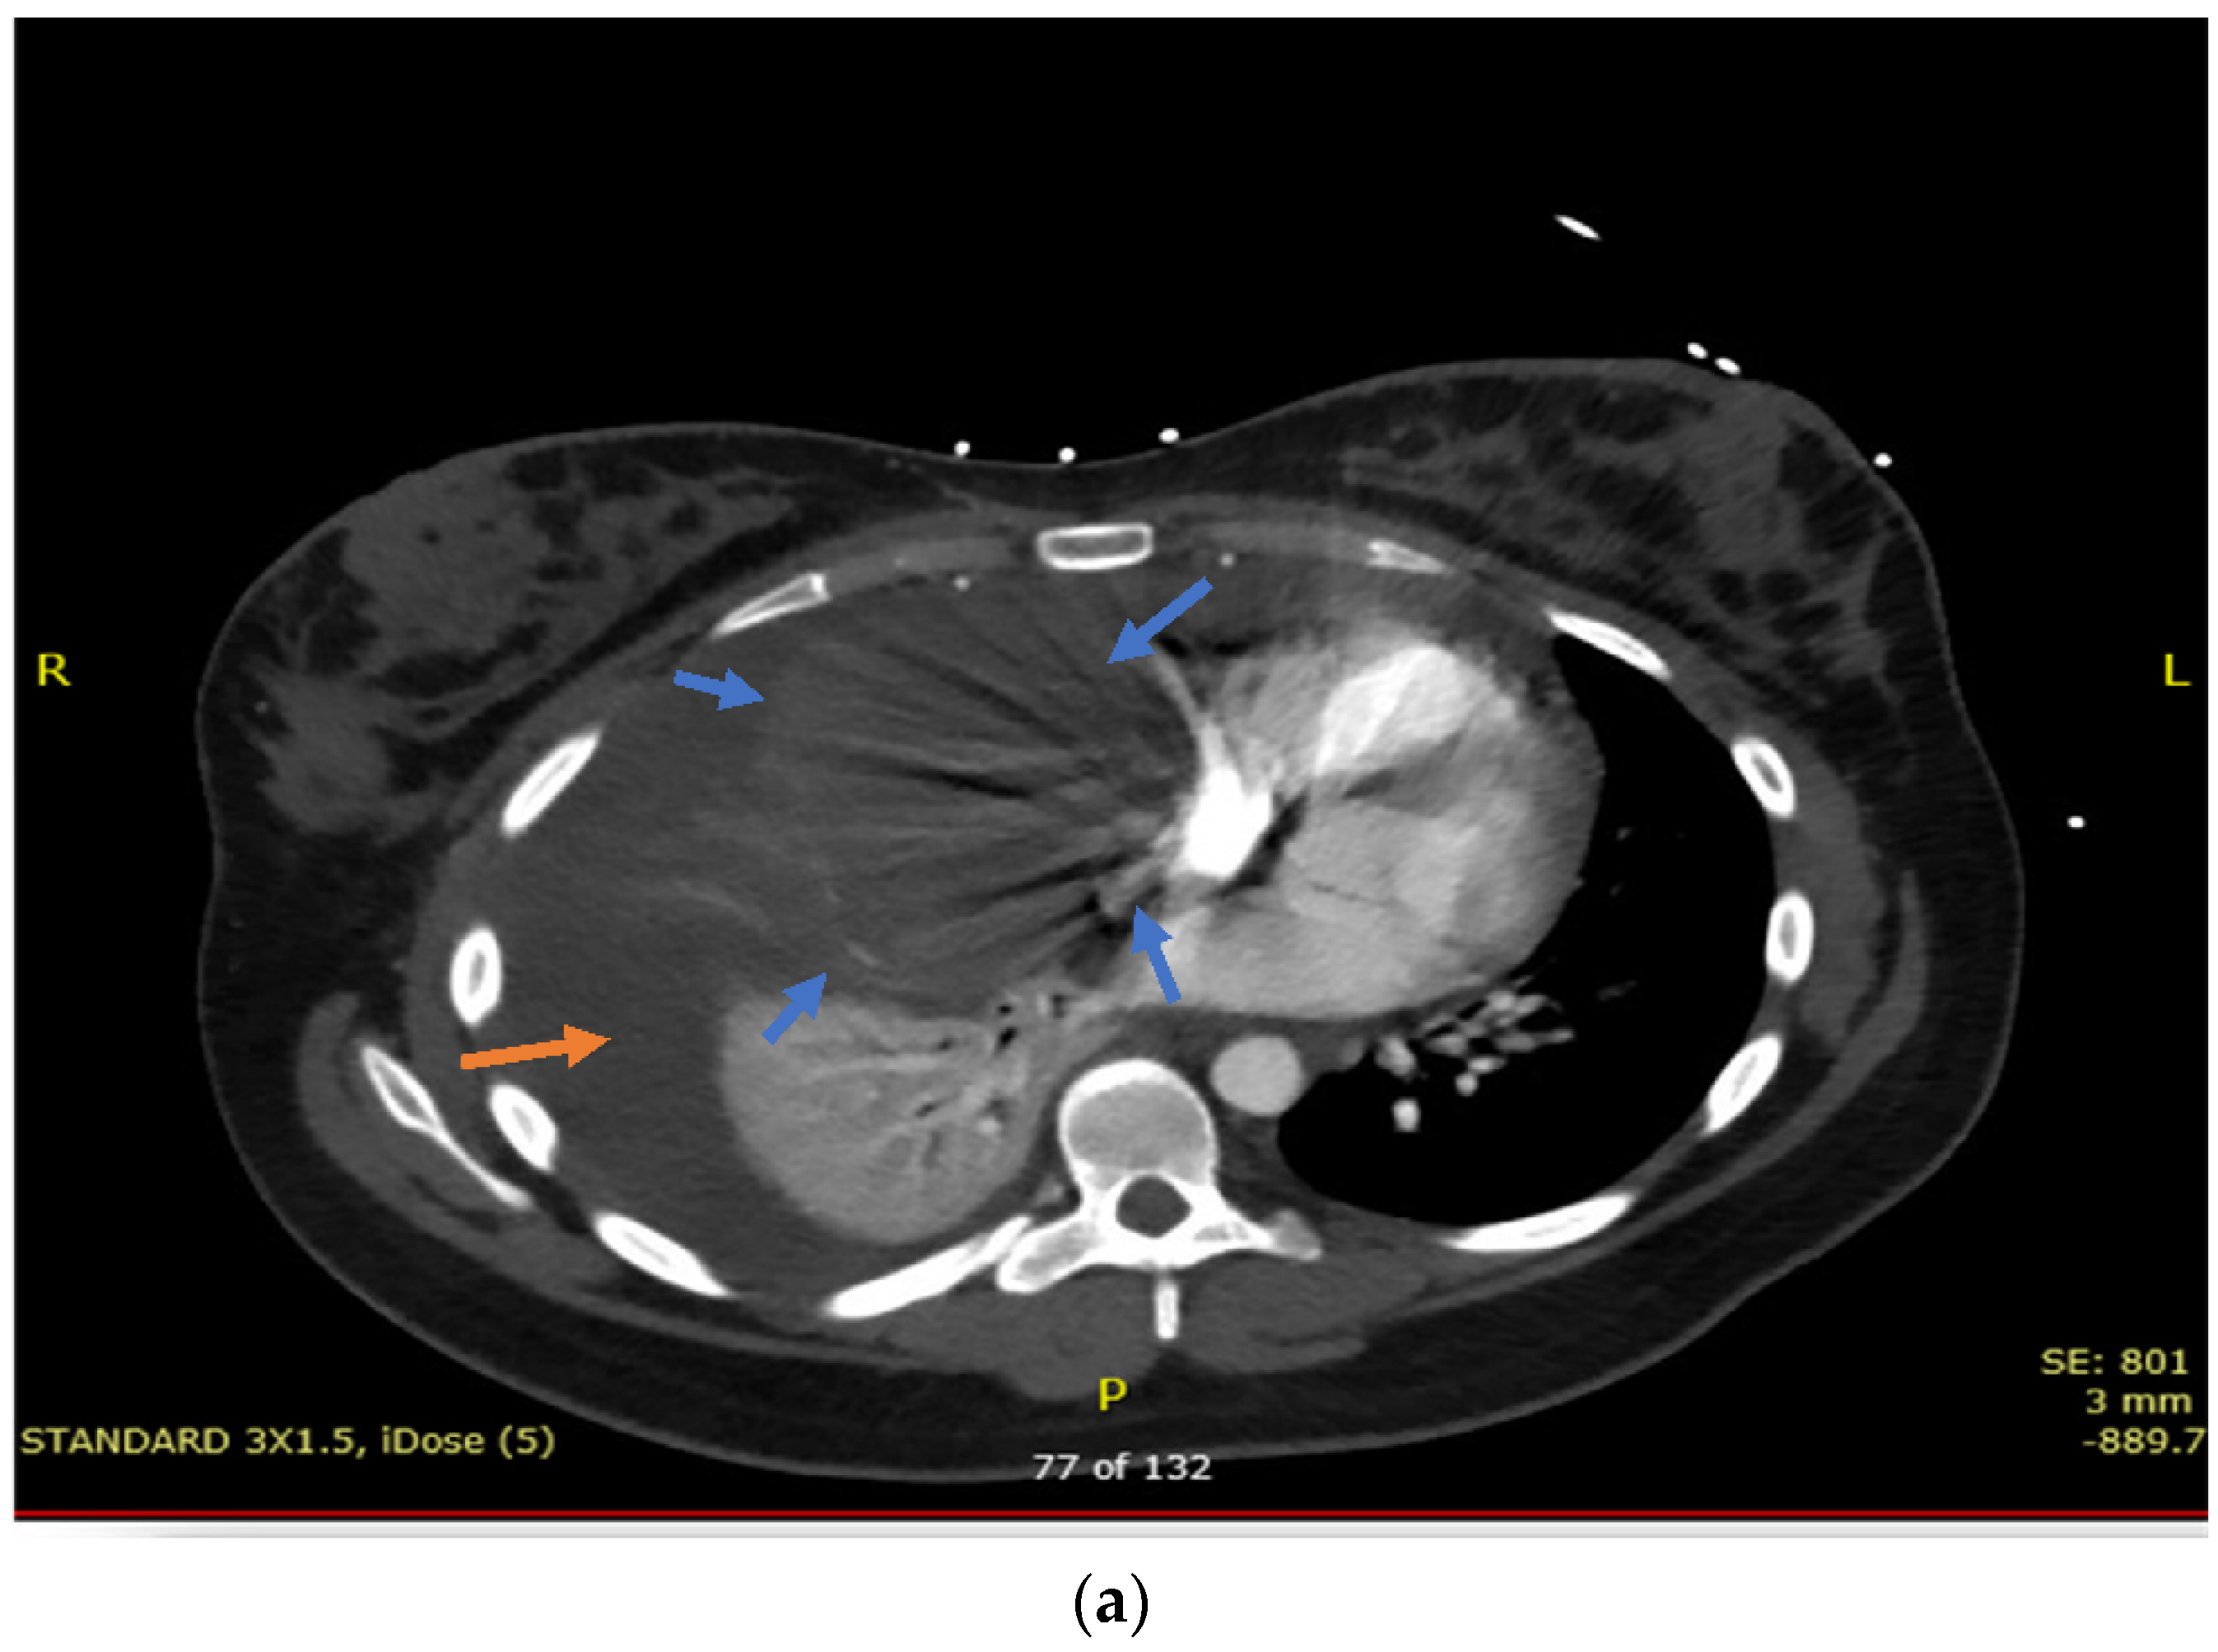

2. Case Presentation